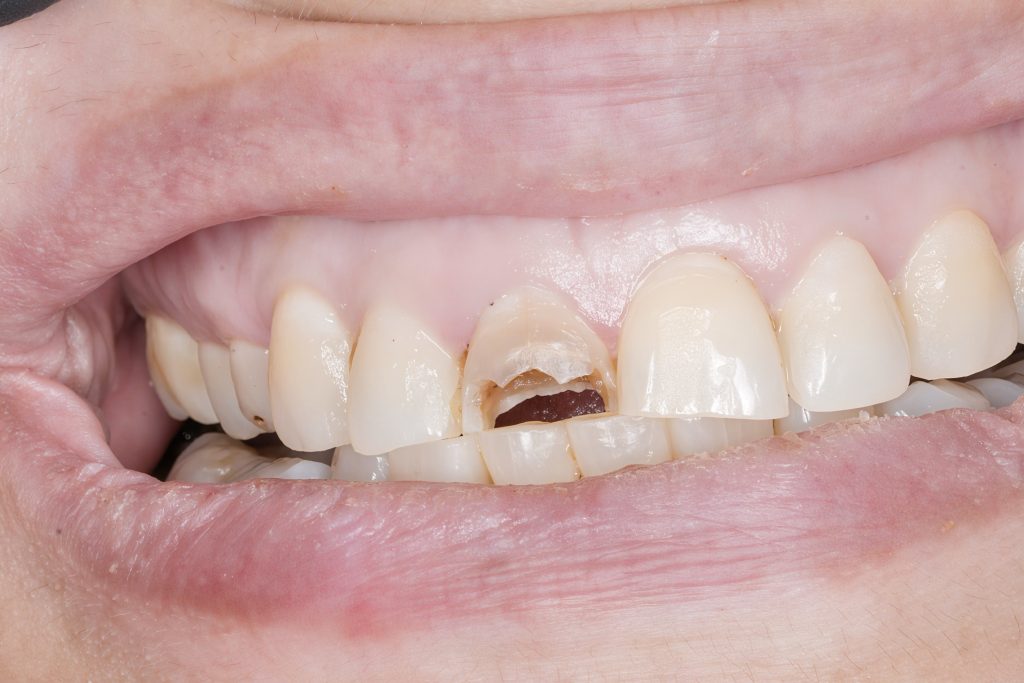

Chief Complaint: Discolored fractured tooth with discomfort on biting

1 Pre-operative Assessment

Clinical exam revealed a coronal fracture exposing previous access and visible sealer remnant. Periapical radiograph confirmed a metallic fragment lodged in the apical third with a faint radiolucency (Fig 1–2).